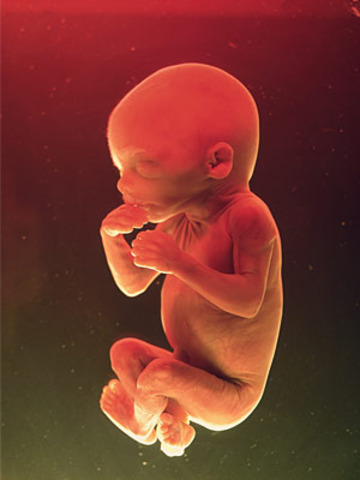

8 weeks

• Week 8

Week 8

The sygote is now designated an embryo. The embryo develops three layers, which form different sets of structures as development proceeds. At 8 weeks, the embryo is one inch long. Photo Cred; Google Images.